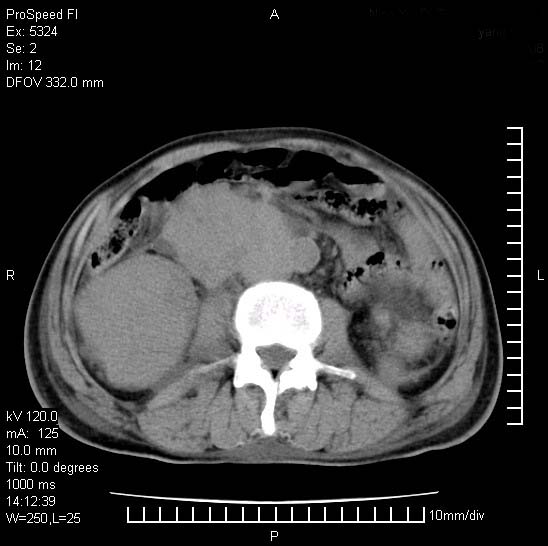

患者阴囊肿大14月,腰痛2个月,咳嗽,咳痰1周,患者现在肾功异常,做增强有些担心,我们用的是欧乃派克.

双肾均有软组织密度舯物,腹膜后淋巴结肿大包饶腔静脉------考虑为恶性占位病变,转移瘤可能。

腹腔积液,双肾均有稍高密度肿块,主动脉旁广泛淋巴结肿大,融合,无显著肿块坏死征像,多考虑淋巴瘤累及双肾,不排除肾癌伴转移(肾癌这么大应该较多坏死了),另阴囊肿大,不知是实质肿大还是阴囊积液,如是是积液,多为腹腔肿块压近睾丸静脉所致,如是是实性的,多为淋巴瘤

阴囊肿大是实质性的么,为什么不扫阴囊,此扫描做的是什么部位,肾脏没包括全,也可以考虑生殖系统肿瘤转移

双肾增大,腹膜后多发肿大淋巴结影.首先考虑淋巴瘤.

双肾癌并腹膜后淋巴结转移

考虑恶性淋巴瘤侵及双肾,腹膜后淋巴结肿大。